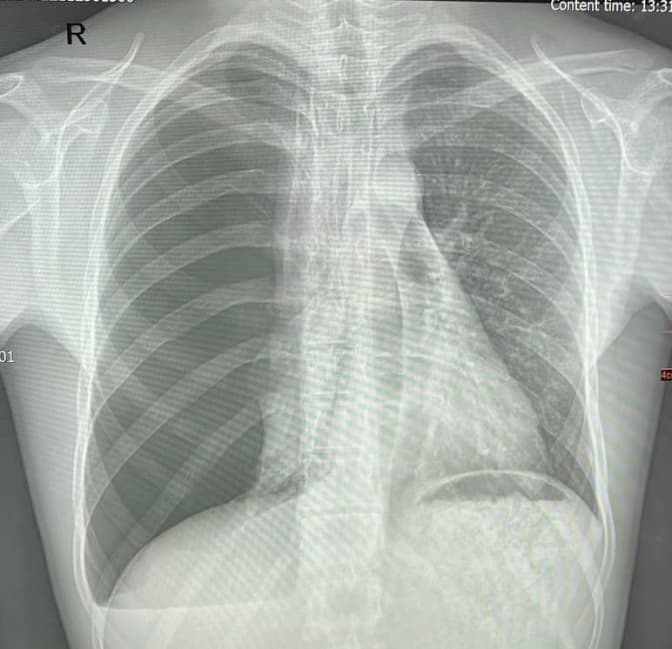

Лікарі львівського Центру дитячої медицини «Охматдит» успішно прооперували 16-річного хлопця із захворюванням, від якого він дихав лише однією легенею. Про це повідомила пресслужба медзакладу.

«У 2017 році, коли Олександру було 9 років – хлопець був шпиталізований до нашої лікарні із правобічним напруженим пневмотораксом. Це коли «рветься» легеня і нагнітається повітря у плевральну порожнину, відтак легеня стискається. Тоді лікарі провели усі необхідні обстеження та виявили бульозну хворобу легень», – йдеться у повідомленні.

Після успішних дій медиків хлопець себе почував добре. Та через сім років під час планового медогляду виявили пневмоторакс. Давність захворювання невідома, адже скарг ніяких у хлопця не було роками.

«Відтак, наші хірурги одразу прооперували хлопця – спершу зробили торакоскопію, а тоді торакотомію. А також атипову резекцію верхньої долі правої легені. Тобто відрізали частину ураженої легені. Усе пройшло успішно! Легеня розправилась, хлопець почувається добре та виписаний із шпиталю», – зазначили у медзакладі.